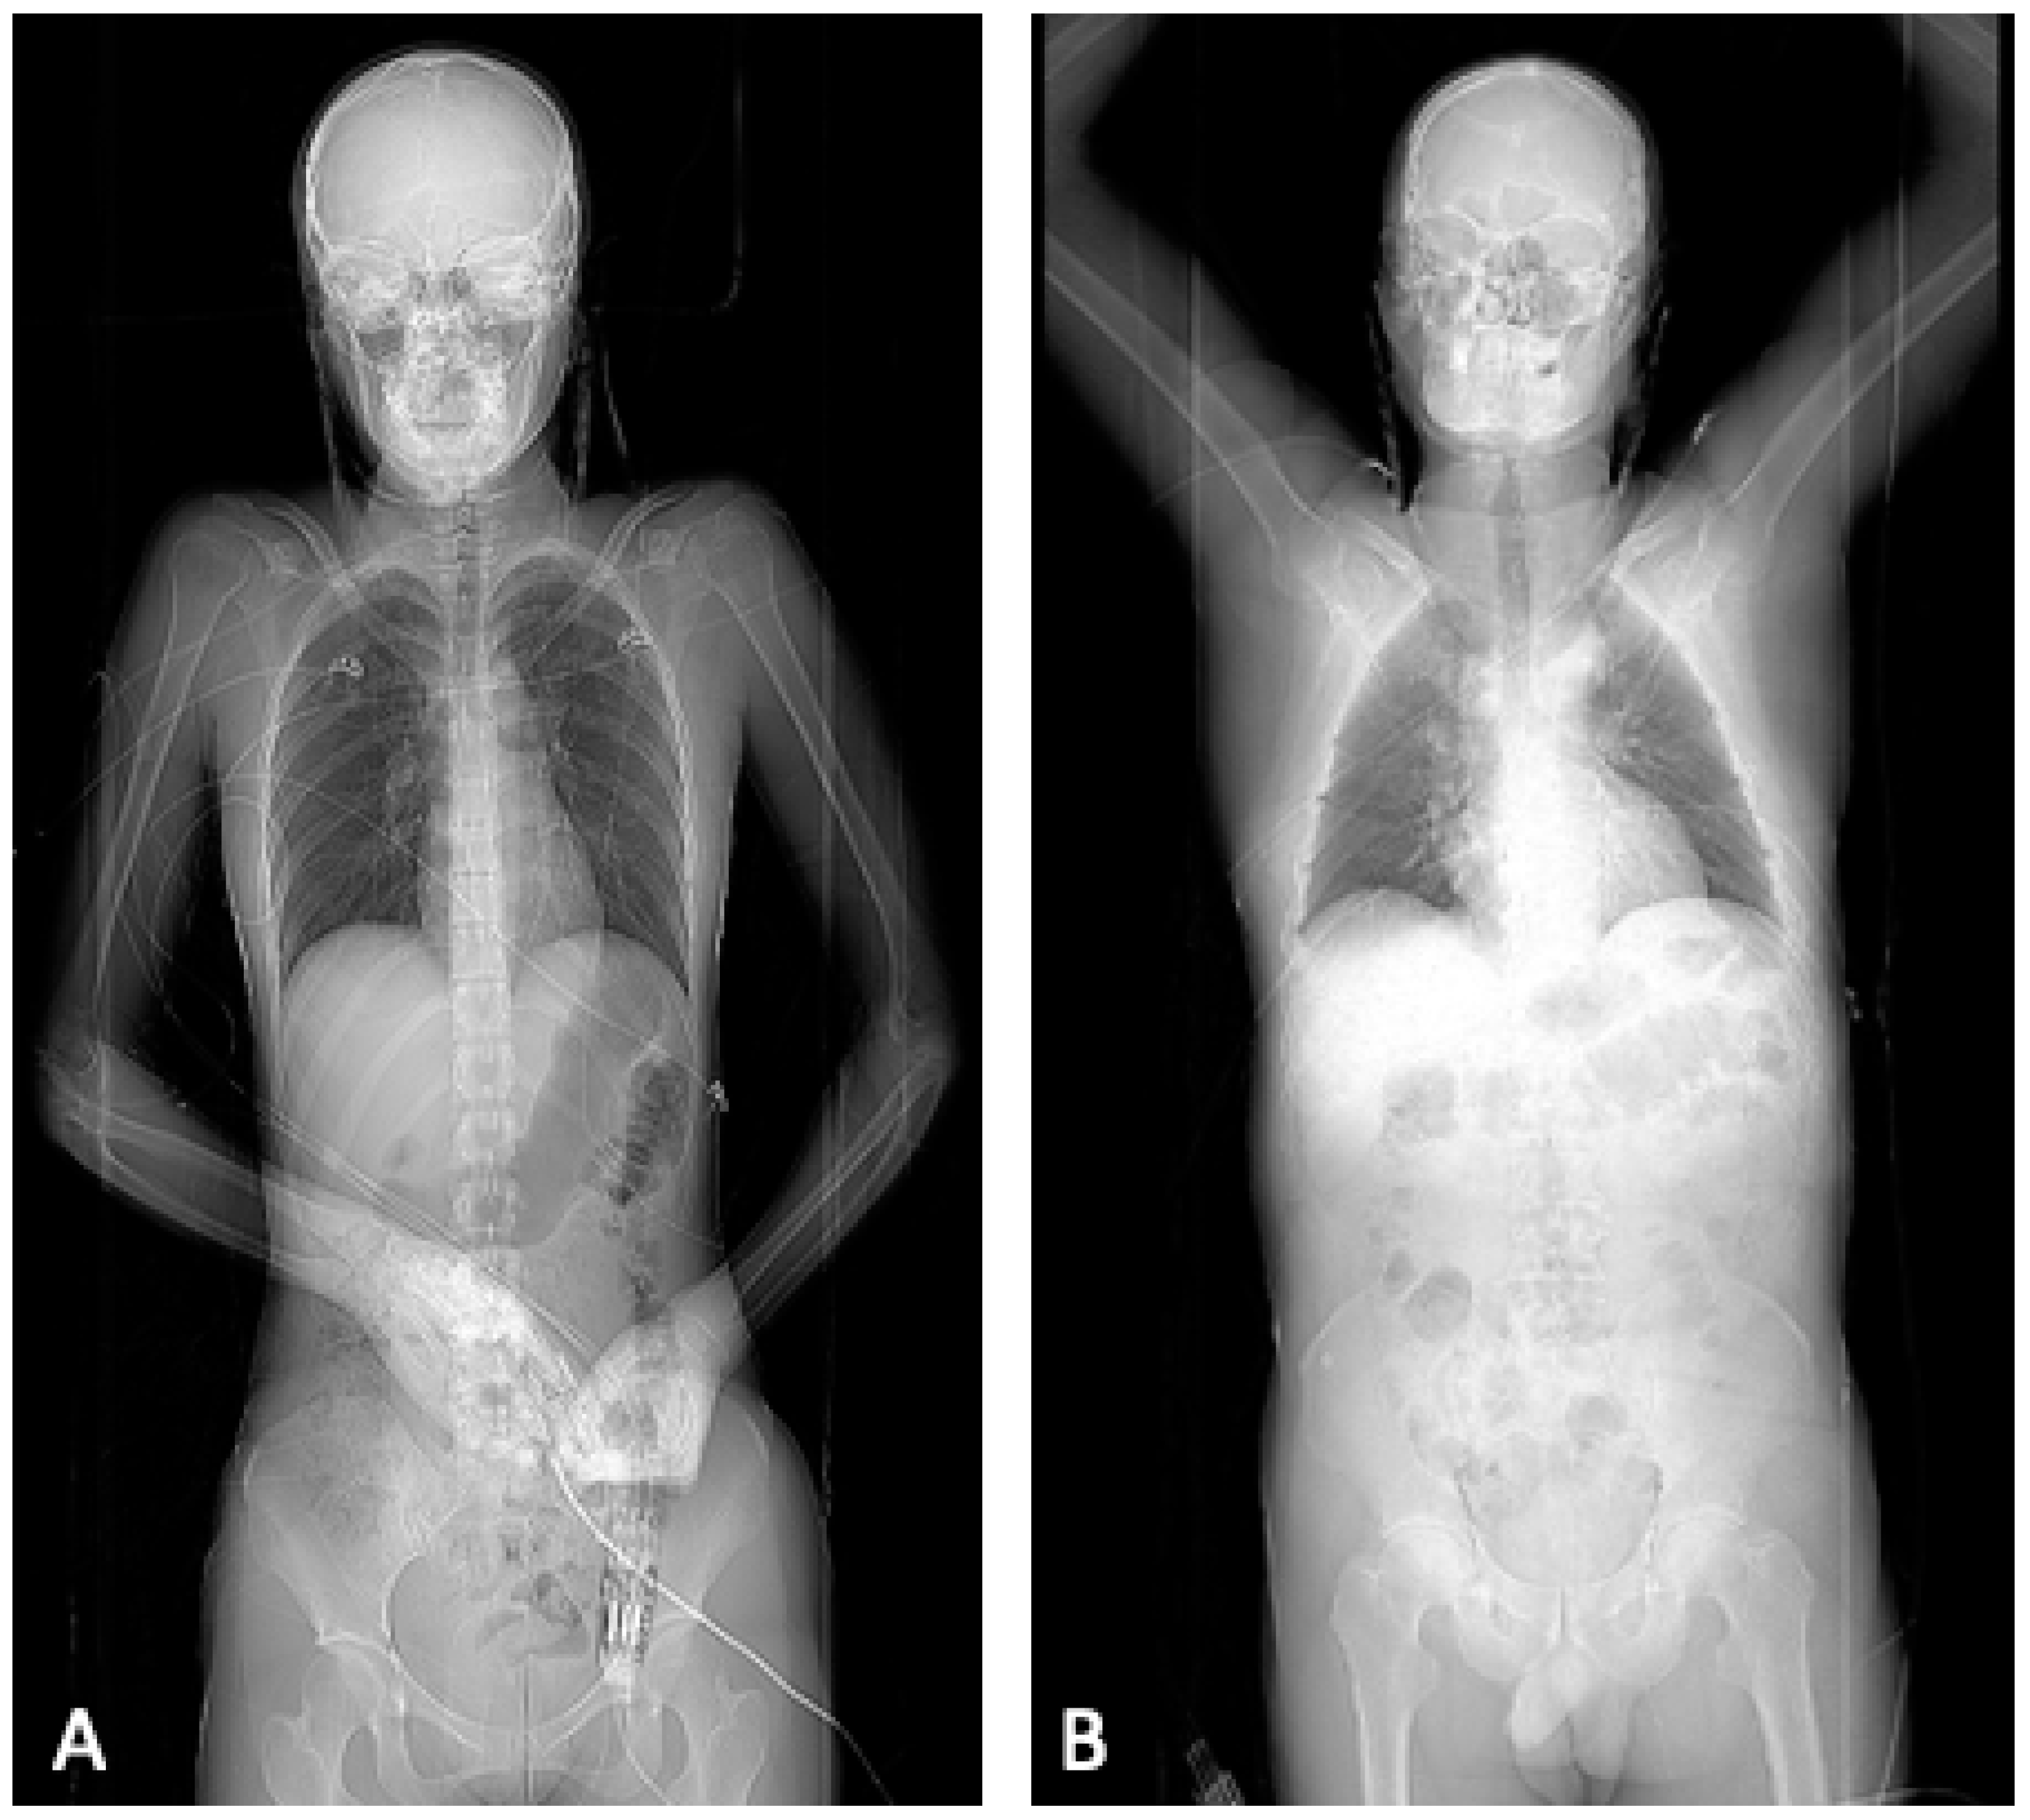

- Protocol A: without repositioning, both arms still in adduction

- Protocol B: relocation and positioning of both arms in elevation